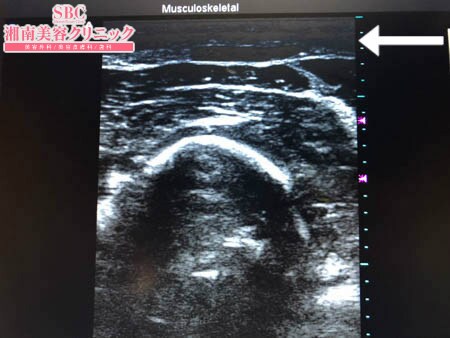

No.206040【脂肪吸引】【動画あり】湘南美容外科脂肪吸引最高責任者である竹田先生による脂肪吸引のフォトギャラリー!スタッフさんからの手術のご依頼は何よりも信頼の証!他院で取り残された二の腕の皮下脂肪をもうひと絞り!術中3Dタッチビュー・左二の腕

決して多くはないものの

皮下脂肪の取り残しを徹底的に

根こそぎ!!

吸引しておきましたので

今回の結果には満足してくださることでしょう。